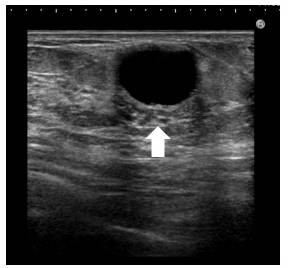

本日は、のう胞型(壊死した脂肪からでる液のたまった風船の様な) のしこりです。

上の図が、超音波で評価した、のう胞状のしこり です。